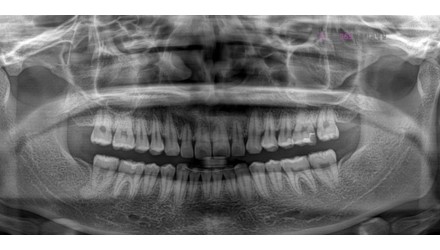

2024.12.05

치료 전